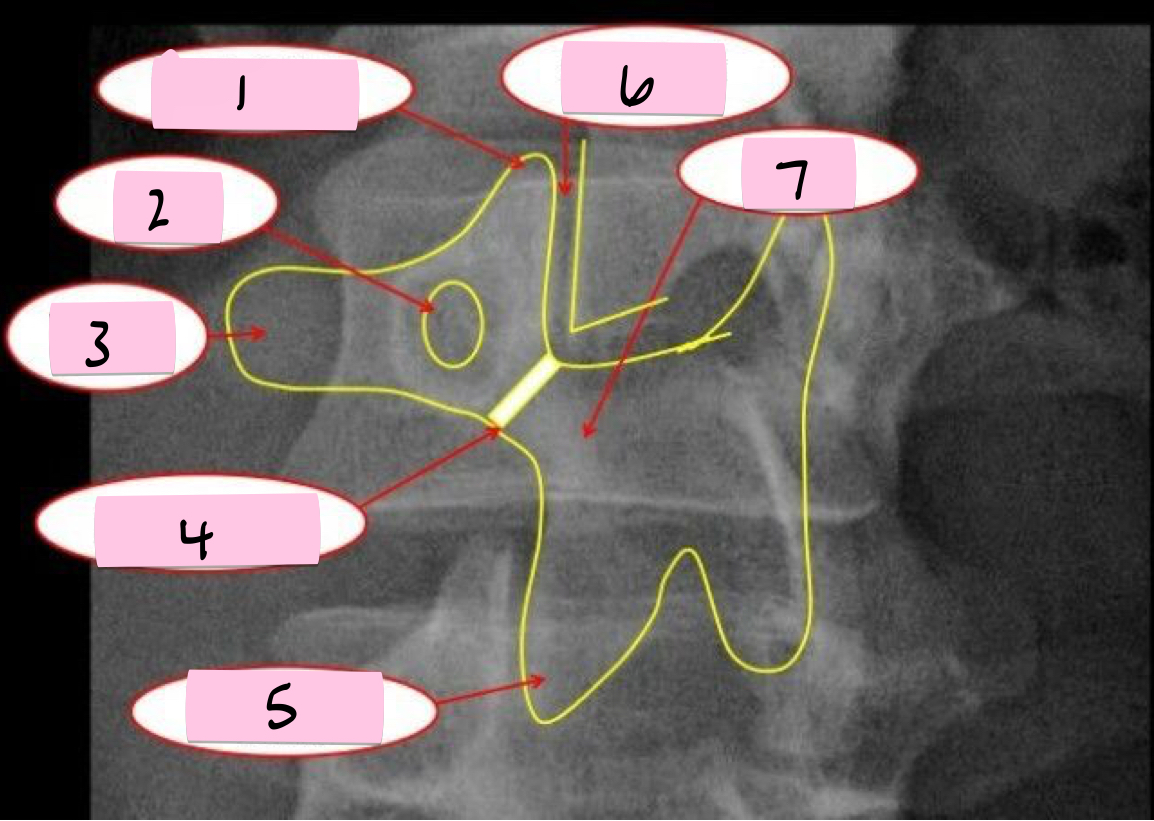

What is 1 pointing to?

Superior articular process

What is 2 pointing to?

Pedicle

What is 3 pointing to?

Transverse process

What is 4 pointing to?

Pars interarticularis

What is 5 pointing to?

Inferior articular process

What is 6 pointing to?

Zygapophyseal joint

What is 7 pointing to?

Lamina